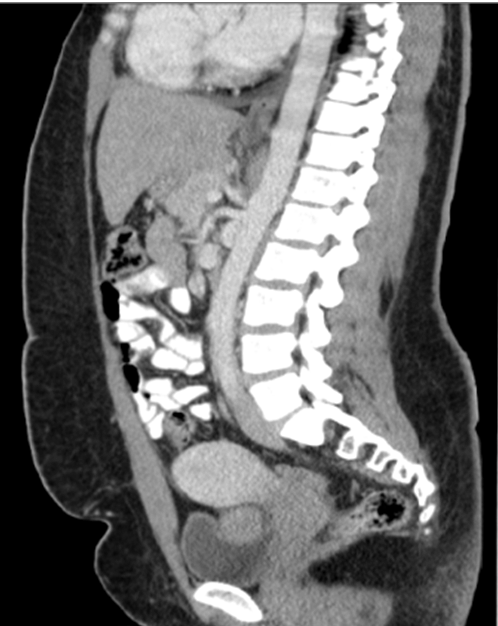

Patient followed with endocrine for continuous hirsutism and clitoromegally. Medical treatment of hirsutism was attempted with minimal response. In 2014, CT scan showed 7 cm adnexal mass with possible recurrence. Patient subsequently got pregnant (Figure 2) and (Figure 3). Testosterone and inhibin levels were still within normal limits. MRI scan showed 8x8x7 cm pelvic mass with cystic changes separate from the uterus (Figure 4) and (Figure 5). Case was discussed in tumor board with the presence of gynecological oncology, medical oncology, surgical oncology, radiology and MFM team. Anonymous decision was made to offer the patient surgery for suspected recurrent granulosa cell tumor of the ovary.

Figure 3: A 30-year-old female with suspected recurrent ovarian granulosa cell tumor in pregnancy. Contrast-enhanced sagital CT image showing heterogenous enhancing pelvic mass measuring 7.3x5x5.4 cm.